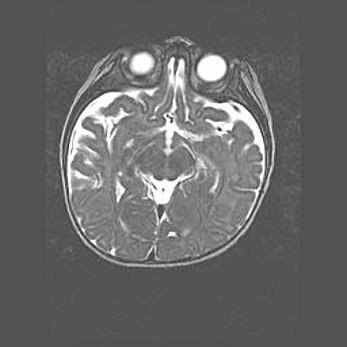

Мальформация Денди-Уокера. Киста задней черепной ямки.

Агенезия мозолистого тела.

Возраст: 2,5 месяца

Вес: 2420 г

Пол: женский

Окружность головы: 37 см

Срок гестации: 32 недели

Мальформация Денди—Уокера — редкий вид патологии ЦНС, представляющий собой врожденный порок развития каудального отдела ствола и червя мозжечка, ведущий к неполному раскрытию срединной (Мажанди) и латеральных (Лушка) апертур IV желудочка мозга. Для этогно синдрома характерна триада симптомов: гипотрофия червя мозжечка и/или полушарий мозжечка, кисты задней черепной ямки, гидроцефалия различной степени. В 70% случаев порок сочетается и с другими аномалиями головного мозга, в частности с агенезией мозолистого тела.